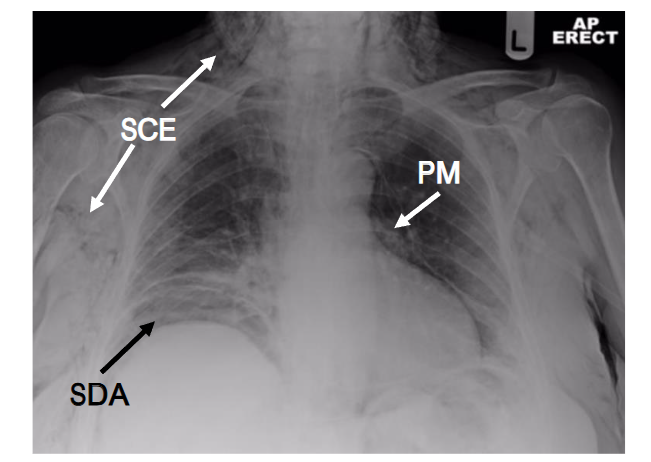

In most developed countries, there is less reliance on simple radiographs but an appropriately exposed radiograph can reveal subcutaneous emphysema clearly (see Figure 1) and may suggest a cause.

Figure 1. Chest radiograph demonstrating subcutaneous emphysema (SCE), pneumomediastinum (PM) and subdiaphragmatic air (SDA).